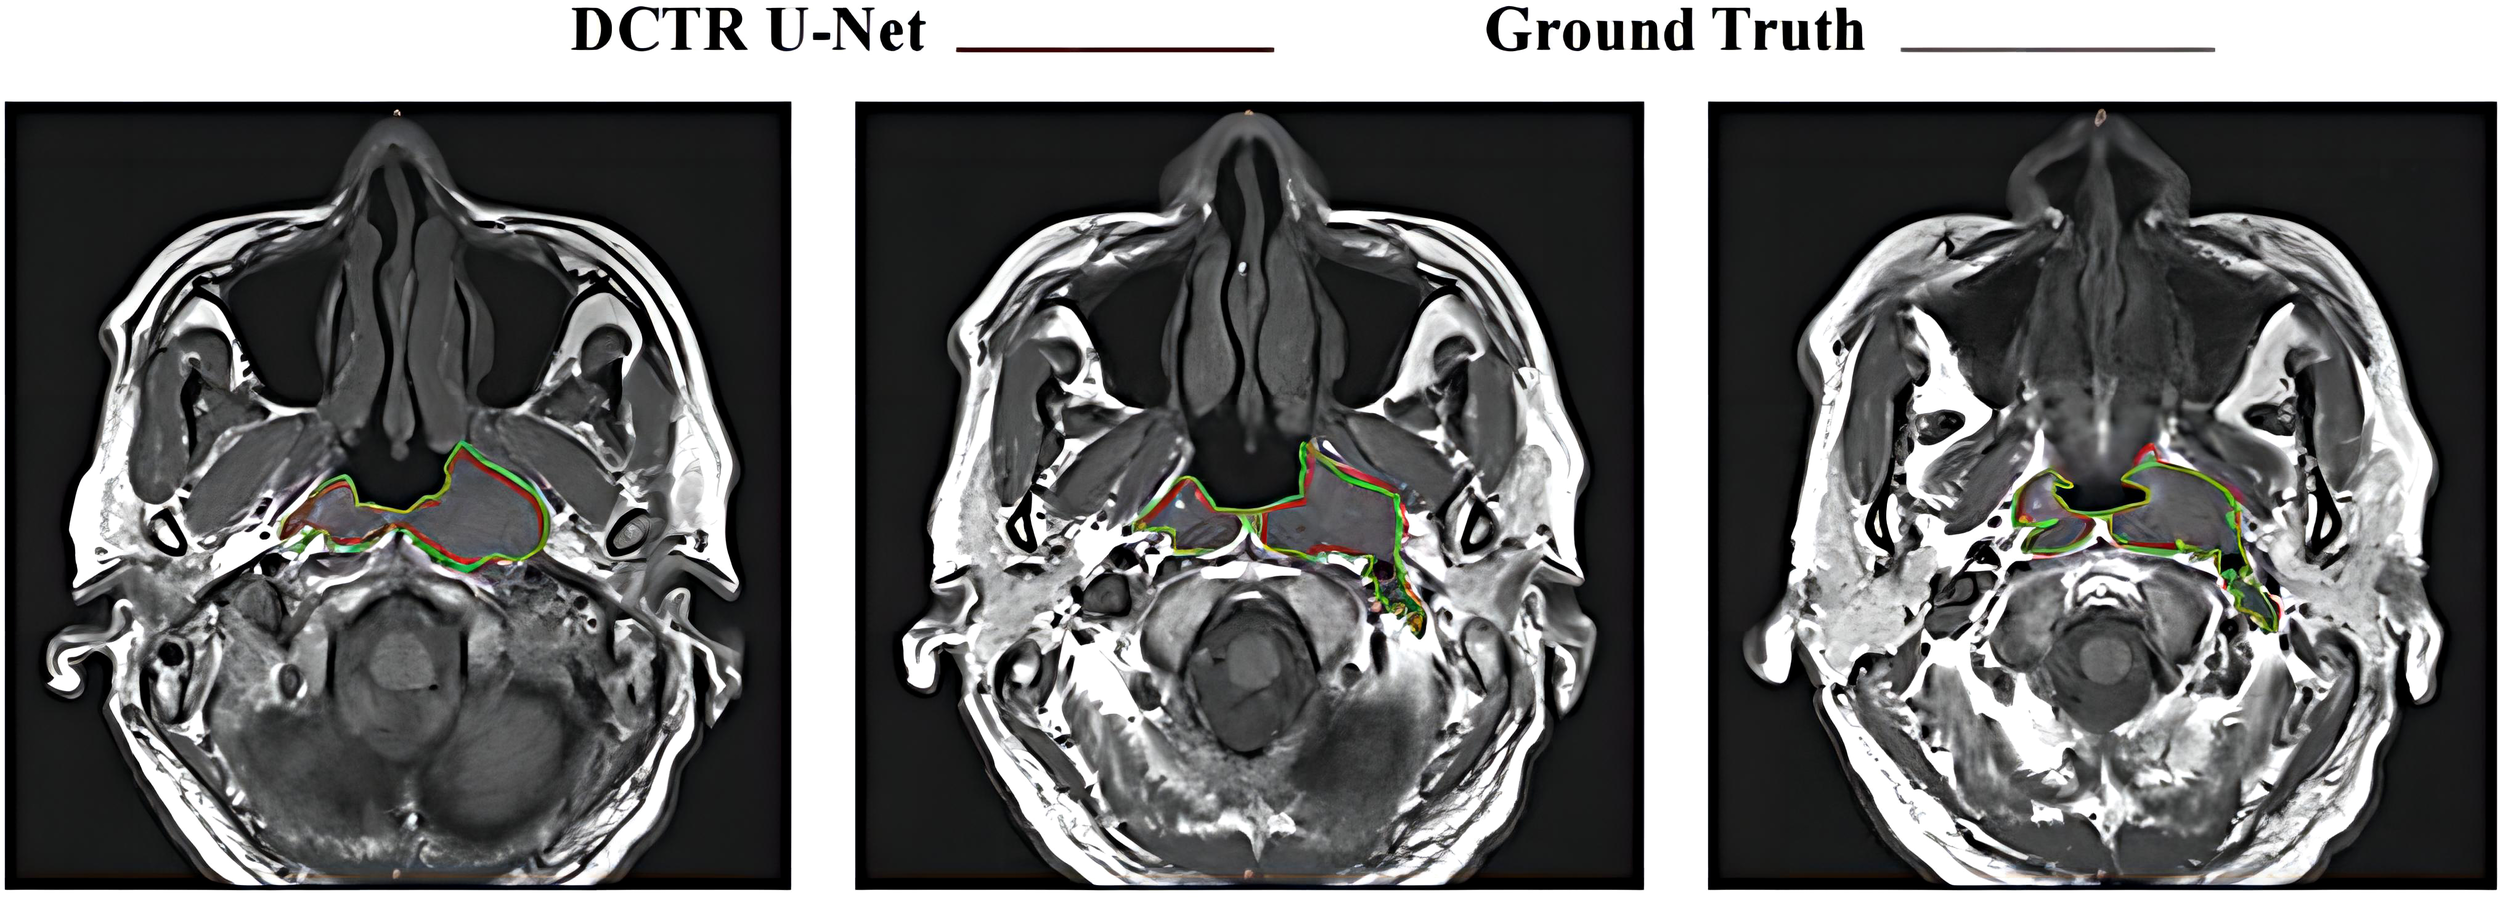

Figure 6 shows the consistency level of NPC tumor volume contour between DCTR U-Net as an artificial intelligence (AI) tool and oncologists. The red line represents the contour generated by artificial intelligence, while the blue line represents the contour depicted by oncologists.

Figure 6

Differences between tumor contours generated by DCTR U-Net and Ground Truth.

From a qualitative analysis perspective, as shown in Figure 6, compared to the tumor contour outlined by oncologists, DCTR U-Net has roughly segmented the overall contour of nasopharyngeal carcinoma, demonstrating good performance. From a quantitative analysis perspective, the DSC and ASSD values of DCTR U-Net are 0.852 and 0.544 mm, while the DSC and ASSD values of Ground Truth are 0.873 and 0.516 mm. Comprehensively consider ing the qualitative and quantitative analysis, we can conclude that there is almost no difference in indicators between these two methods of analysis. There is a high degree of consistency between the contours depicted by oncologists and those generated by the model.